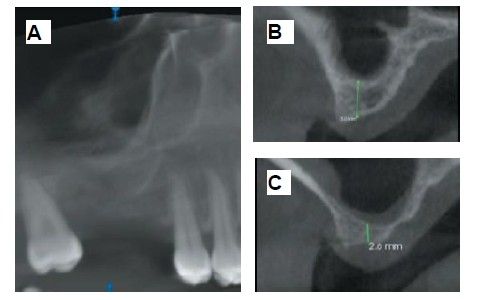

The medical history revealed no relevant medical or surgical antecedents, no known drug allergies, and no harmful habits. Intraoral examination revealed the absence of 1.6 and 1.7, and the presence of 1.8 and 4.8 (Figure 1). Radiographic examination using cone beam computed tomography (CBCT) revealed a residual height of 5.0 mm at 1.6, where an implant could be placed simultaneously, and 2.6 mm in the region of 1.7, making simultaneous implant placement with the lateral approach sinus elevation difficult (Figure 2).